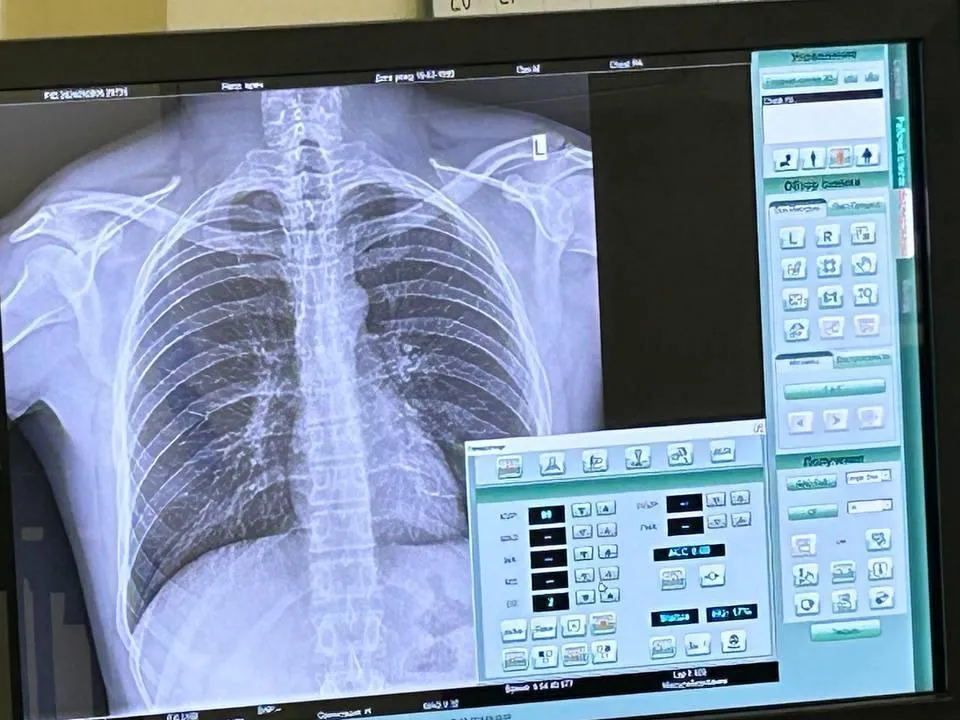

В Центре амбулаторной онкологической помощи в Мытищах провели обследование всех желающих. Проверить здоровье приехали не только мытищинцы, но и жители соседних муниципалитетов – Пушкино и Щелково. Врачи осмотрели всего 140 человек, трех направили на углубленные исследования.

Жителей принимали узкопрофильные специалисты, среди которых – стоматолог, гинеколог и онколог. Они провели ряд диагностических исследований для обнаружения тревожных признаков онкозаболеваний. Вместе с тем, посетители получили возможность сдать анализы, проверить ВИЧ-статус и пройти вакцинацию от гриппа и пневмококковой инфекции.